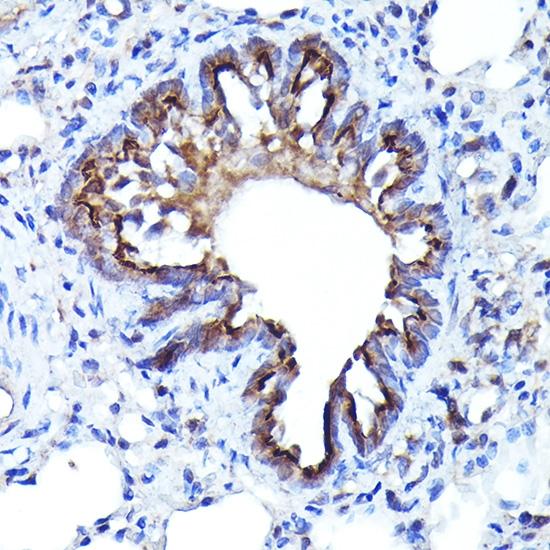

Immunohistochemistry analysis of paraffin-embedded Rat lung using LGR5/GPR49 Rabbit pAb at dilution of 1:300 (40x lens).